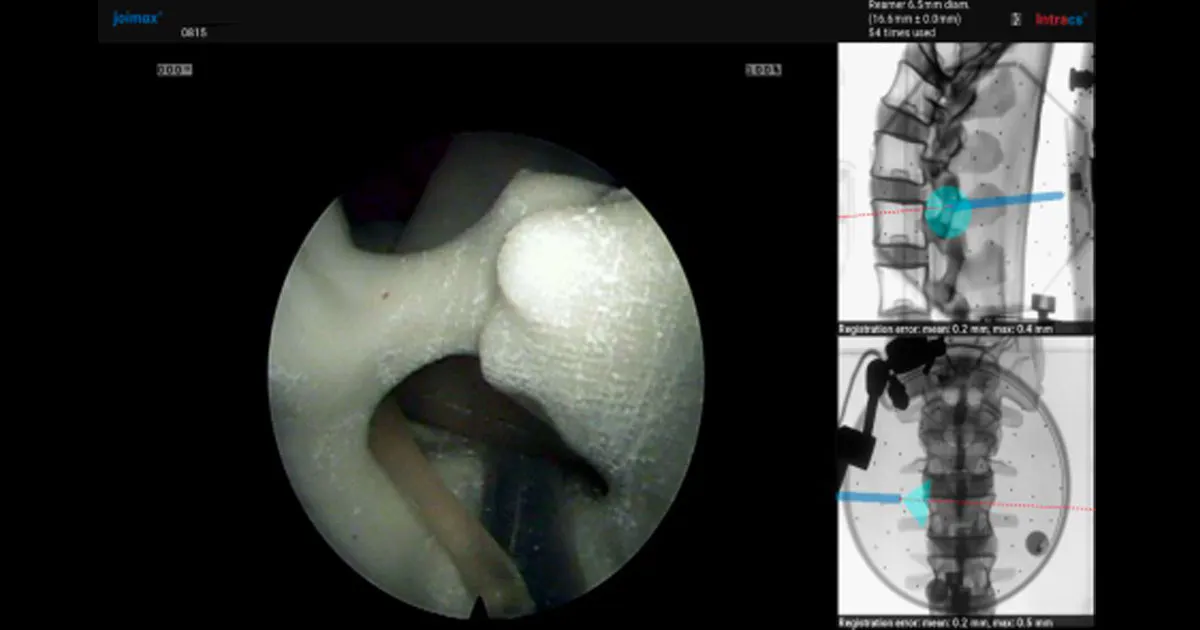

Today, modern navigation technology allows surgeons to visualise the position of the endoscopic instruments as they are placed in the patient’s body, adding to patient safety and reducing radiation exposure to the patient and surgical personnel. Using this technology, interbody cages and pedicle screws can now be used in these Endoscopic Lumbar Interbody Fusion (Endo-LIF) procedures.